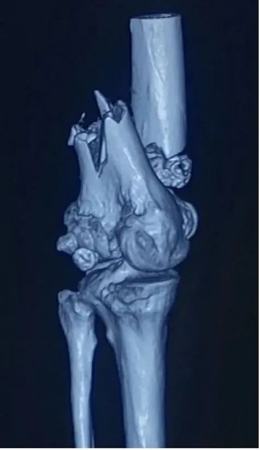

患者是一位高龄女性,因一次滑倒意外致左膝关节受伤,由此导致左股骨远端骨质疏松性骨折,伤后来到积水潭医院创伤骨科住院治疗。

吴新宝团队对患者检查后发现患者系典型老年骨质疏松性骨折,膝关节周围有明显老年退行性改变;股骨远端大量骨性增生导致骨折部位解剖形态与青壮年成人有明显差异,股骨前弓明显增大;同时老年患者骨愈合能力下降,容易发生骨折不愈合,内固定物失效等并发症。如何更好地解决老年骨质疏松性骨折这一临床问题,降低手术并发症是骨科医生面临的一个临床挑战。

经过吴新宝团队对患者病情进行综合分析,拟采用当前骨科治疗前沿的3D打印技术,为患者定制个性化内固定接骨板进行骨折内固定治疗。利用爱康医疗的医工交互系统,爱康医疗研发工程师团队与吴新宝团队紧密互动,根据患者患肢影像资料,专门设计了个性化定制的解剖型股骨钢板。